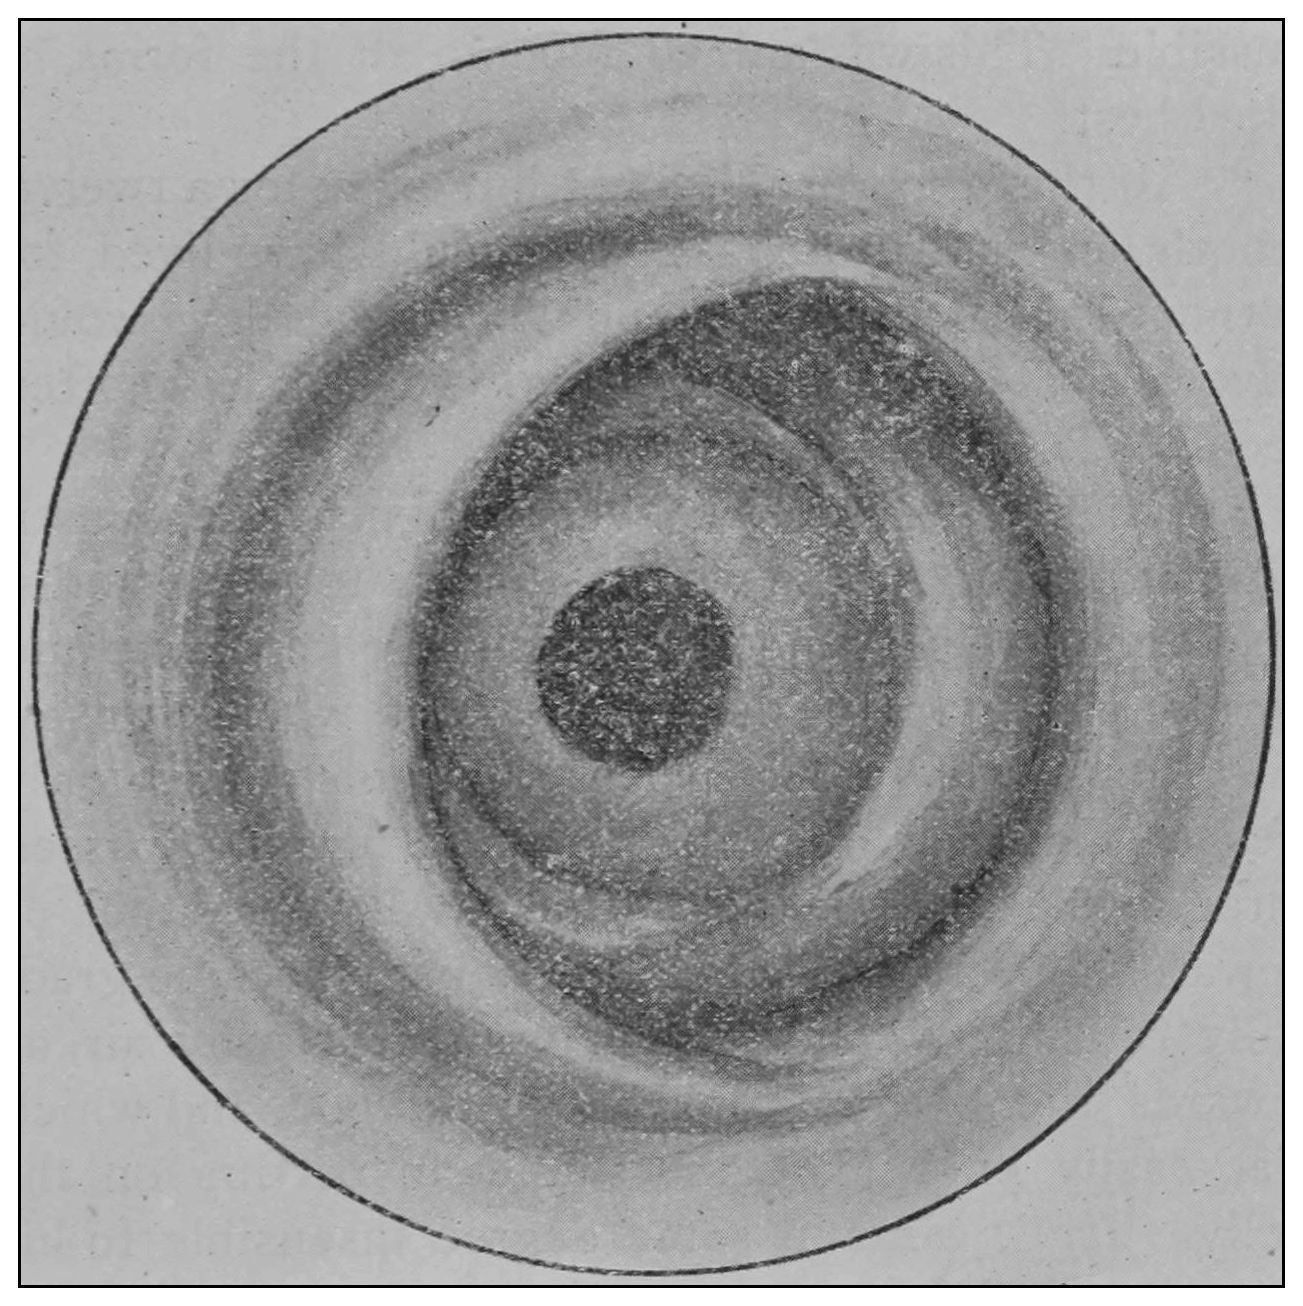

The rectum may present to the eye of the imaginative observer the appearance of a chain of urinary bladders, communicating one with another by means of irregularly elliptic openings set at varying axes, and bounded by the nonparallel borders of the rectal valves. In the normal rectum the air-pressure smooths the mucous membrane evenly over the entire surface of the gut, as may be observed in the photographic illustrations. The normal mucous membrane of the so-called ampulla appears at first wet and of a shining bluish gray. As it dries, under the influence of gravitation the blue venous tint fades out of the gray and the wall assumes a pink tint.[39] Presently it acquires the appearance of parchment, and sometimes it appears painted at rare intervals with ramifying little arteries which may be crowded and overlapped by the larger companion veins; the latter are less arborescent and more suddenly dive and disappear in the bowel-wall. In time, over all there comes a sheen and the vascular pictures may fade away. These phenomena appear exactly as described only in the healthy rectum. In the diseased organ the color varies much.

The photographic reproductions here published are documentary evidence of the existence of the obstructions under discussion. The sketch, Fig. 33, which was drawn from the valve while under the microscopic lens, exhibits the character of these obstructions and proves it that of a typic anatomic valve, and the absence of permanent bands of any other character in this organ is evidence that the semilunar valves and the so-called plica transversalis recti, Falten des Rectums, sphincter ani tertius, superior sphincter, and detrusor fecium muscles are one and the same thing and this thing is essentially a valve. It is most prominent when the gut is most distended.